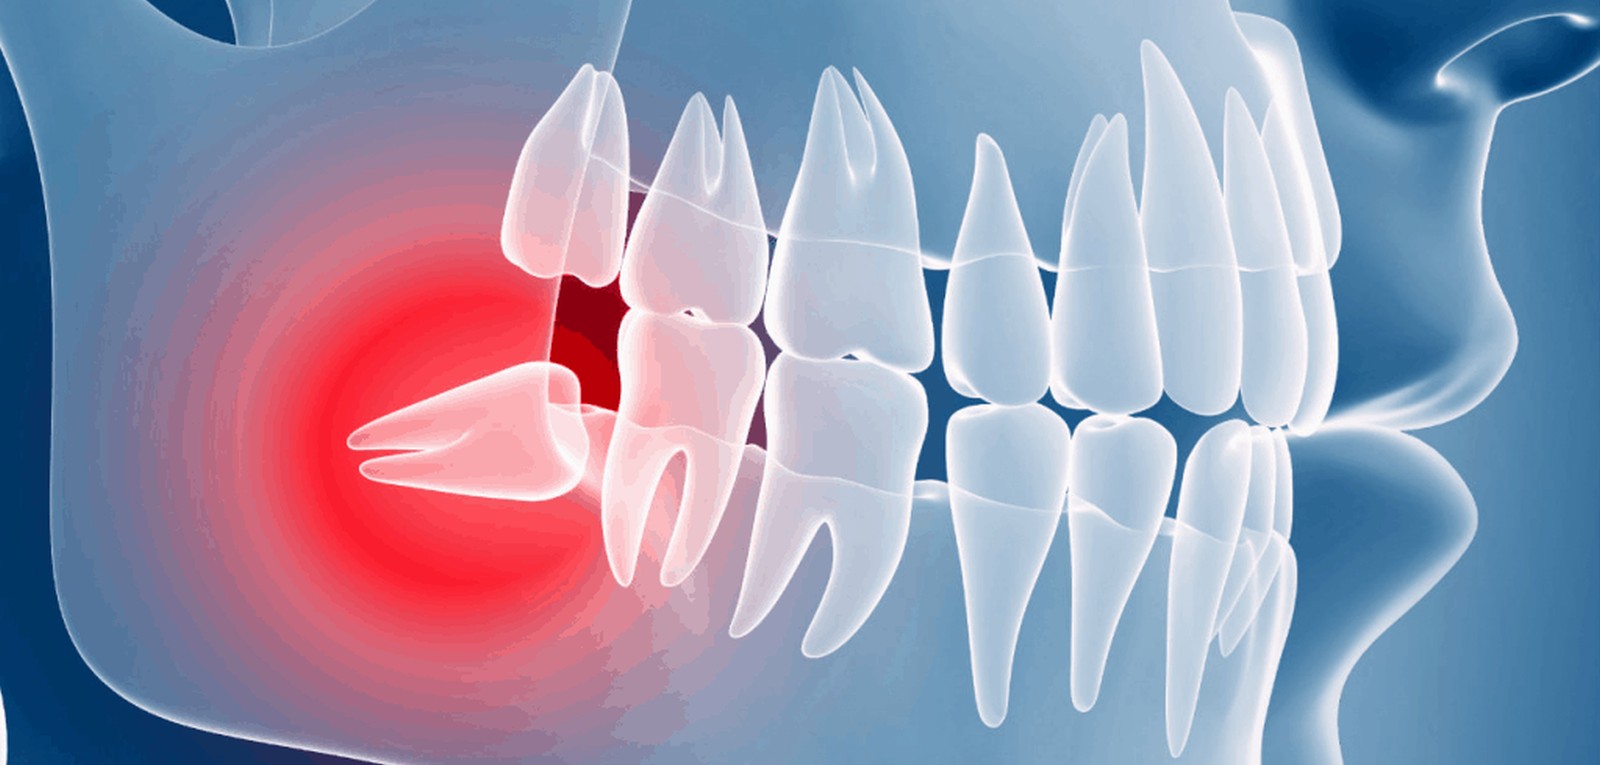

Sometimes, your wisdom teeth don’t come through properly, meaning they’re impacted. This can cause problems such as pain, swelling and infection. Having your wisdom teeth taken out can ease these symptoms.

Sometimes though, the way an impacted wisdom tooth is positioned can make it easy for food and bacteria to get trapped around the gum. This can lead to swollen and sore gums (pericoronitis), tooth decay and infection. If you’re having problems such as these, your dentist may recommend taking the impacted tooth out.